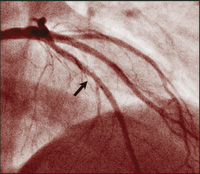

Though there have been similar case reports,17,18 ours is a unique example of an angiographically proven very late stent thrombosis, 3 years after placement of DES. During angiography 9 days prior to the event, no abnormality was noted within the previously implanted DES, nor at the stent edges before the cessation of clopidogrel therapy. Nine days after stopping therapy with this drug, filling defects were seen (Figure, B).